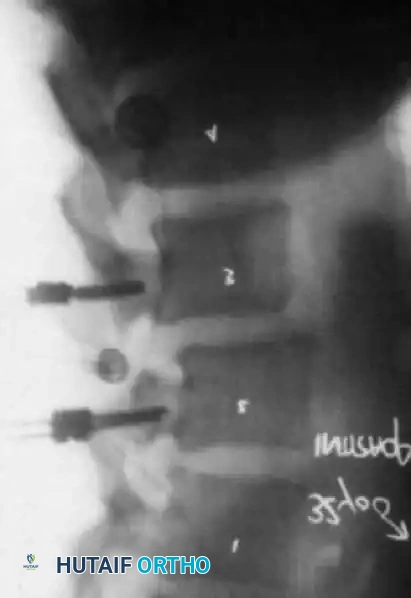

Intraoperative/Postoperative lateral radiograph demonstrating the trajectory of pedicle screws stabilizing the spondylolisthesis.

- Rod Contouring and Reduction: Titanium or Cobalt-Chrome rods are contoured to the desired lumbar lordosis. In cases of spondylolisthesis, reduction of the slip can be achieved via the instrumentation, though partial reduction is often sufficient and safer for the nerve roots. In degenerative scoliosis, compression on the convexity and distraction on the concavity aids in coronal correction.